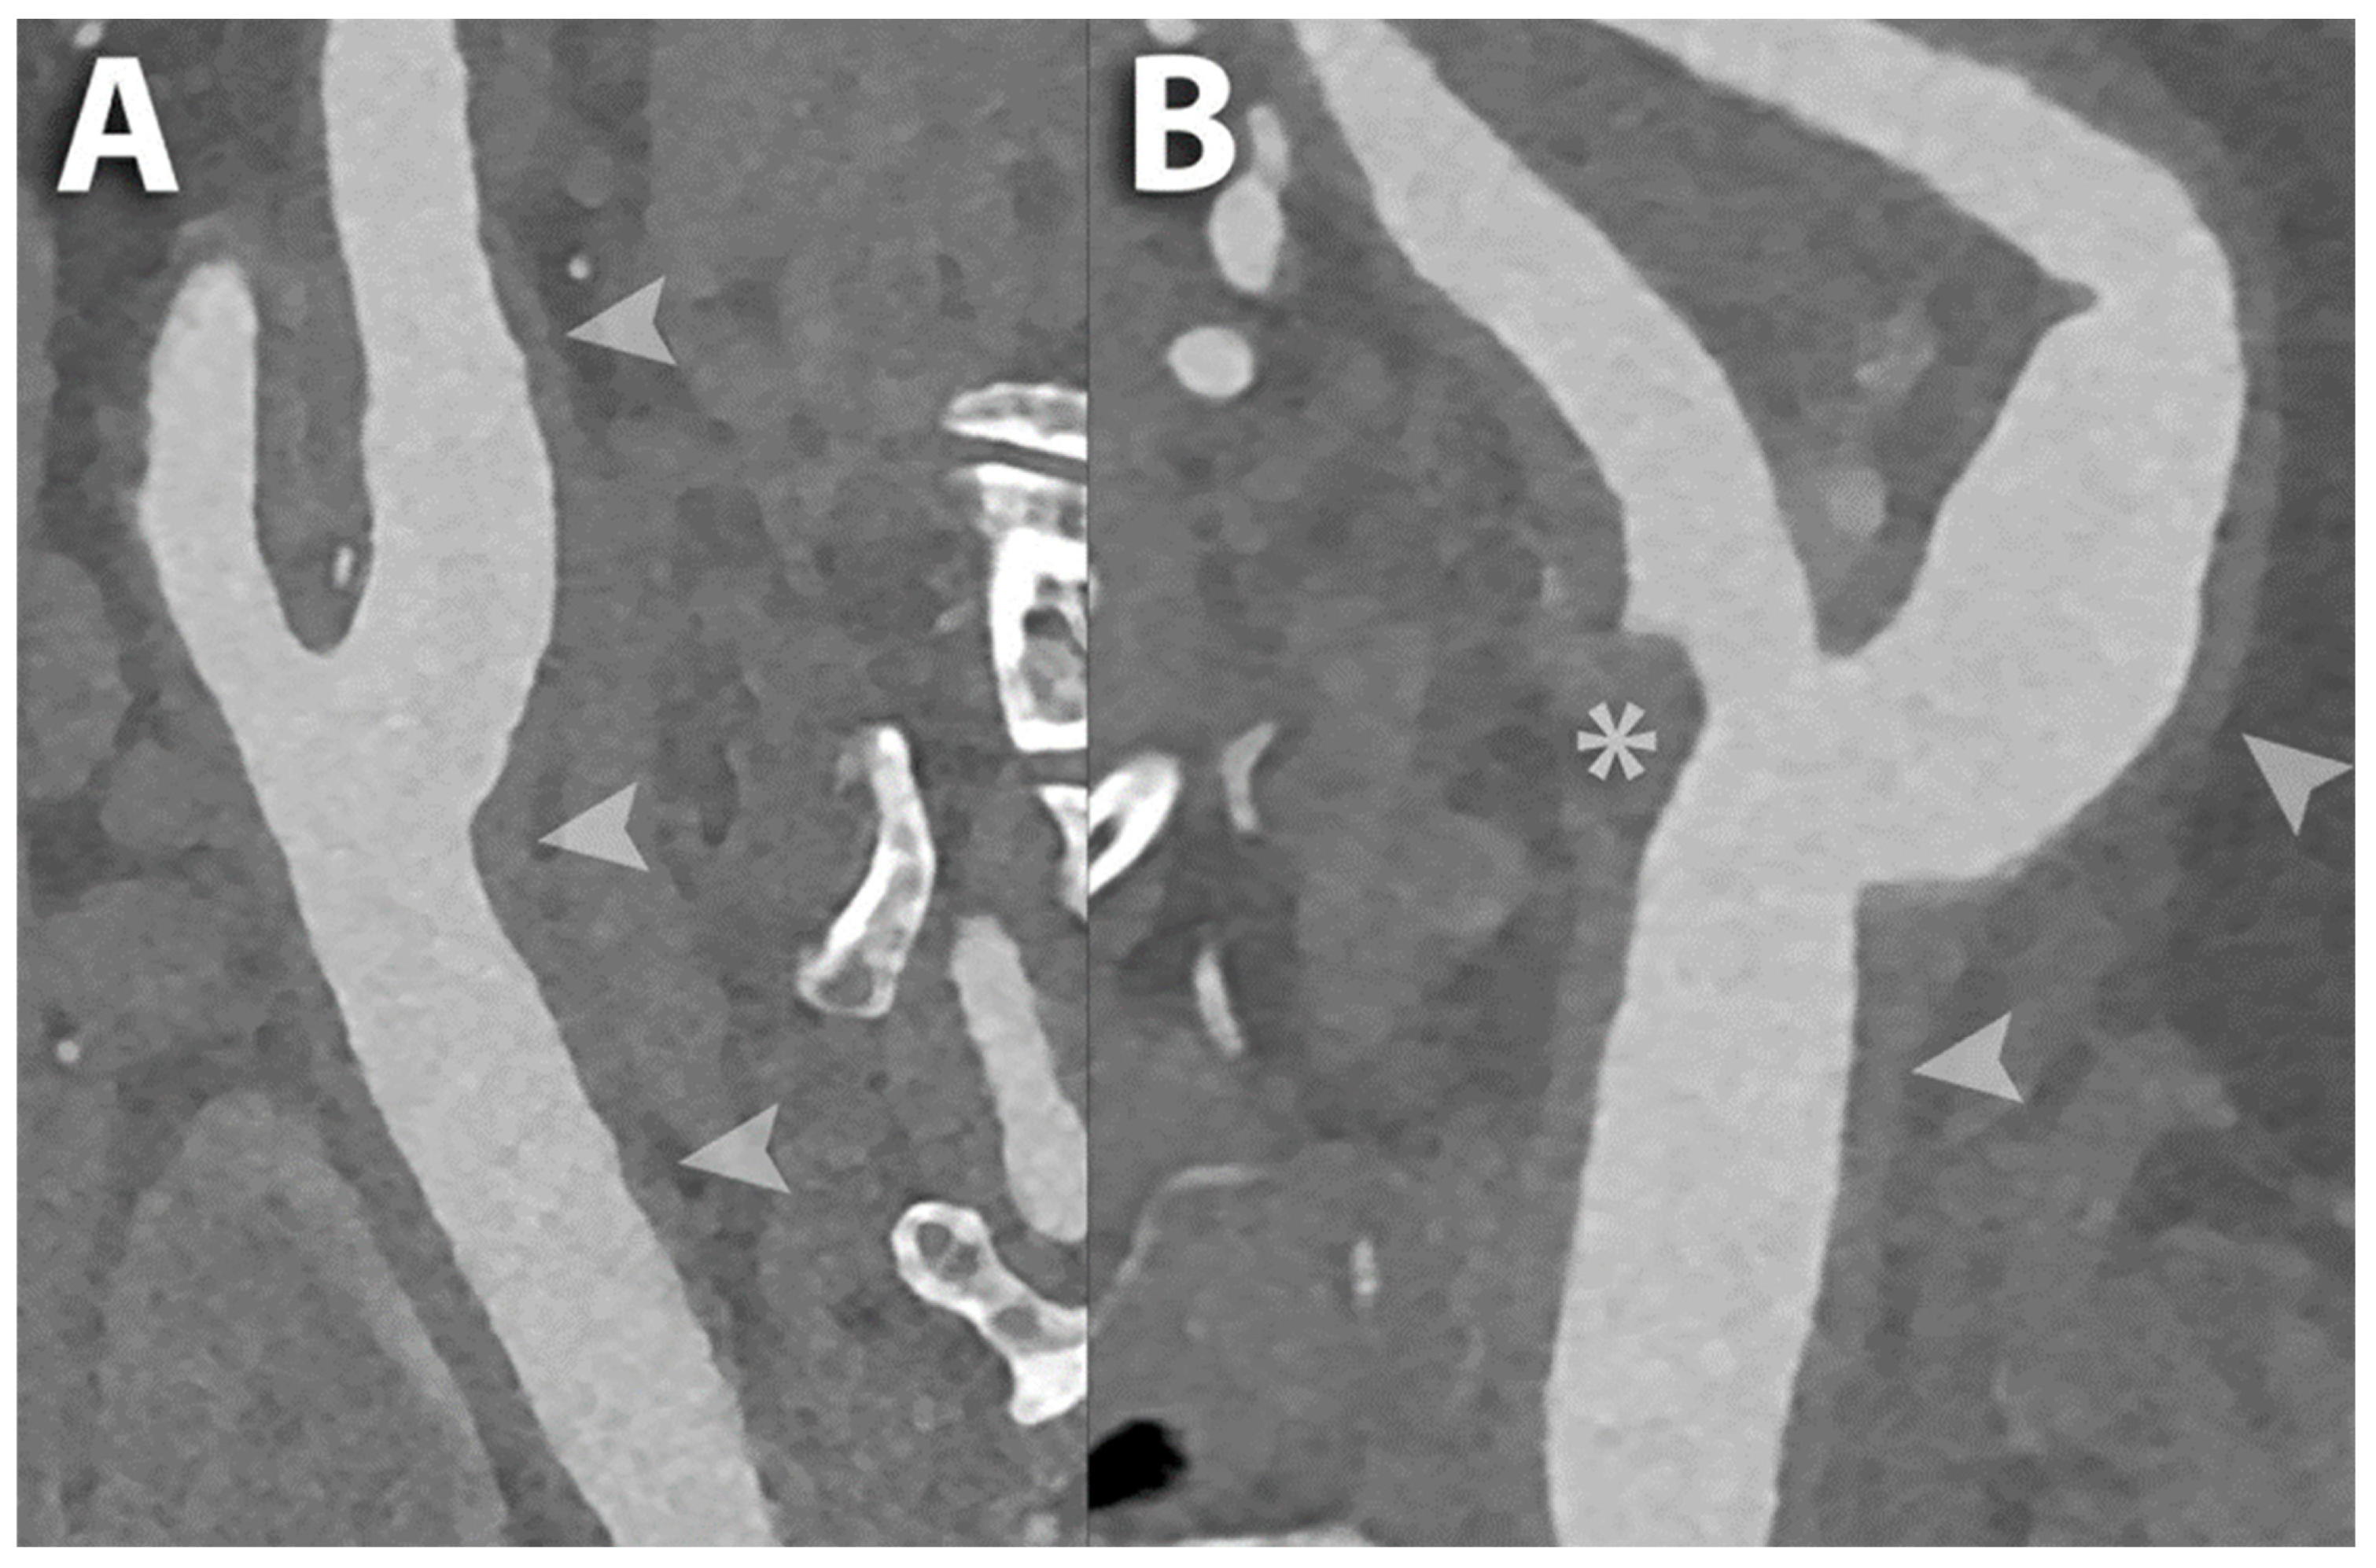

6.1. Carotid Lumen Evaluation

6.2. Carotid Stents